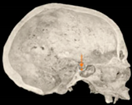

Three points determined the Acta plane: O, F right (FR), and F left (FL) (Table 2). Point O is the midpoint between the most craniodorsal point of the dorsum Sella and the most posterior dorsal point of the Basion in the midsagittal plane (Figure 1). Both points F are a result of the intersection between two lines: the line that connects the most inferior points of the lower orbital margins, right and left, and a line perpendicular to this line that runs through the most external points of the orbital margins, right and left (Figure 2). The new transverse reference plane, the Acta plane (Figure 2), is created by connecting the O-point (Figure 1) with FR and FL (Figure 2).

Figure 1.

Point O (green dot) is the midpoint between the dorsum Sella (Se) (red dot) and the Basion point (Ba) (yellow dot).

When determining the internal reference of the skull, the aim was to determine an origin point in the midsagittal plane, as previous studies have confirmed the consistency of the landmarks in the midsagittal plane [17,34]. At first, the midpoint between the left and right anterior clinoid processes was considered as the origin point. However, the left and right anterior clinoid processes have been reported as a reference with low reliability [35], and they were asymmetric in dry skulls as well as in many CBCT images from this sample. The second option was to use the most anterior border of the dorsum Sella. However, the Sella landmarks (Sella, Sella inferior, Sella posterior) are highly dependent on the DICOM orientation [17,35,36]. On the other hand, the most superior-posterior point of the dorsum Sella seemed more accessible and less orientation-dependent on the CBCT images. However, after using this point to align the CBCT scans, the final head position rolled too far backward. This issue was probably caused by the excessively high position of the dorsum Sella relative to the F-points. To address this discrepancy, the origin point was set in a lower position. One of the options considered was the Basion point. However, its position was too low in regard to the F points, which resulted in a forward-rolled skull after reorientation. As a result, the midpoint between the Basion and the dorsum Sella was adopted as the origin point, named point O.